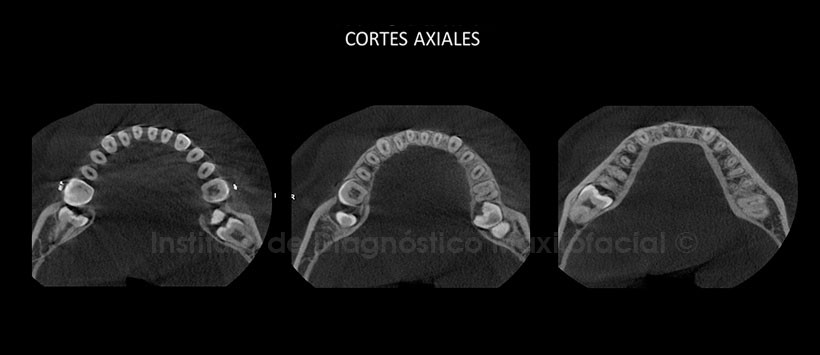

A la evaluación de la CBCT en cortes axiales (Figura 2), transaxiales (Figura 3 y 4) y tangenciales (Figura 5 y 6), se evidencia: la raiz mesial de la pieza 3.8 se encuentra en estrecha relación con la cortical superior del conducto dentario inferior. Se evidencia tambien el segmento apical de la pieza 3.7 en contacto con la cortical superior del conducto dentario inferior; así mismo se descarta la aparente reabsorción radicular visualizada en la radiografía panorámica, con la corona proxim hacia la tabla ósea lingual. Pieza 4.7 intraósea, segmentos radiculares en estrecha relacion con el conducto dentario inferior que a su vez se encuentra en contacto con la tabla ósea lingual. Adicionalmente se aprecia en el maxilar superior a la pieza 1.7 próximo hacia la tabla ósea palatina.